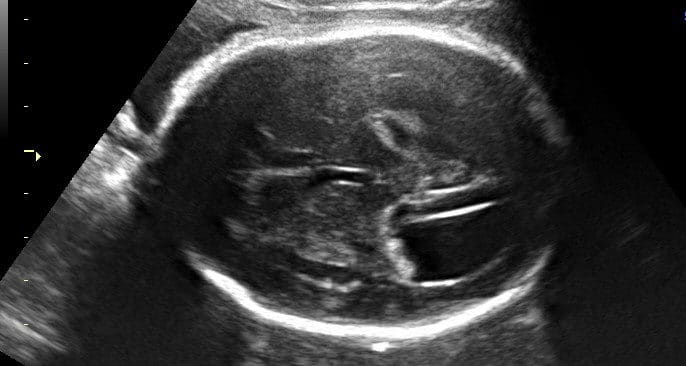

Agenesia de corpo caloso é uma má formação congênita que se caracteriza pela ausência (agenesia) do corpo caloso, com o…